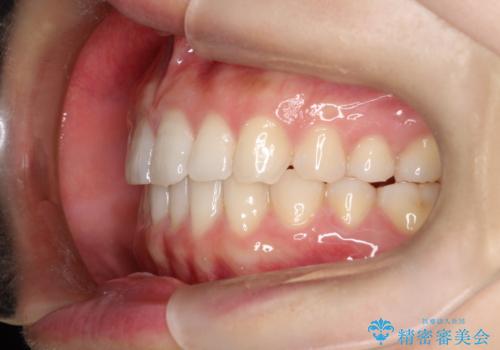

治療前は臼歯部反対咬合のため下顎が偏移し正中がずれていましたが、臼歯部反対咬合を改善したことで、正中のズレを改善することができました。